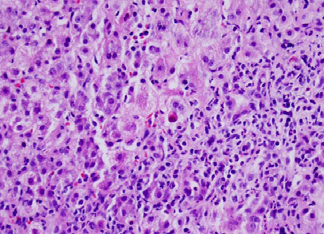

The liver biopsy (see Figure 1)

Figure 1: The liver parenchyma has necro-inflammatory changes with apoptosis (arrow) and Kupffer cell hyperplasia. Lymphocytes are predominant, but other inflammatory cells such as plasma cells, eosinophils, and neutrophils are also present. There is no evidence of fatty change, Mallory bodies, epithelioid granuloma formation, viral inclusions, stainable iron, or malignancy.

showed acute parenchymal inflammation with necrosis and minimal portal fibrosis. Although immunoperoxidase stains for the viruses did not reveal any definitive inclusions, the patient’s adenovirus blood PCR detected a viral load of 5192 copies/mL. The patient improved without intervention, with AST 92, ALT 151 within one week of discharge and neurologic status returning to baseline. He is now clinically well, one year later.